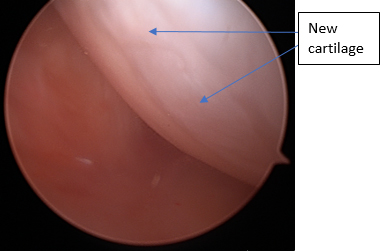

Next, small holes are drilled or punched into the bone to create bleeding. The idea is for a blood clot to form and fill the area where the cartilage defect has occurred. The blood clot will then be gradually filled with cartilage producing cells that will replace the blood clot with cartilage. Normally this new cartilage is not as good as the original cartilage but will be better than having no cartilage there.

Cargel is a biologic agent that is added to a small amount of blood taken from thee patient and is injected onto the area of microfracture. In some studies, it has been shown to increase the quality and quantity of cartilage regrowth compared to microfracture alone.

Cargel is layered onto area

Step 6:

cartilage regrowth 1 year later